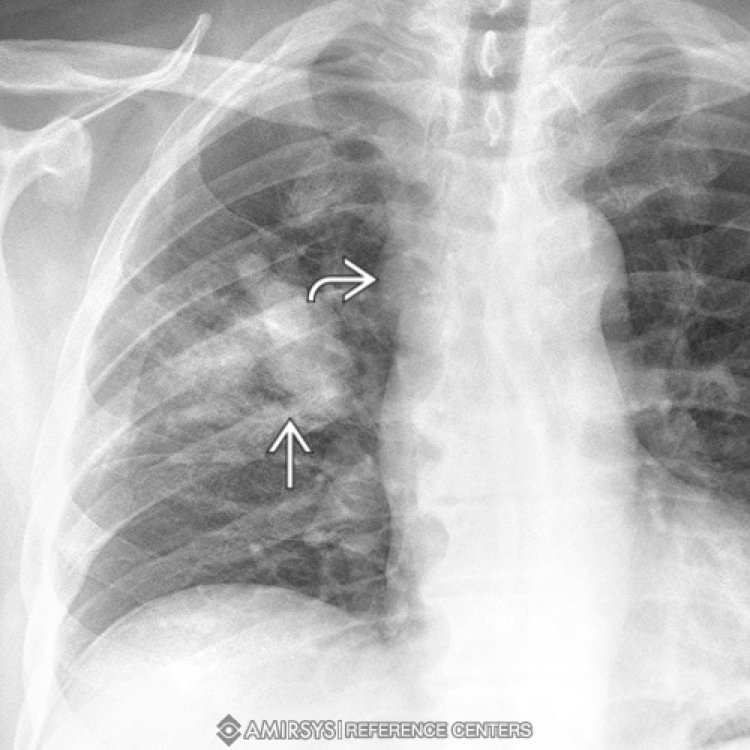

What type of lung cancer is this?

squamous cell carcinoma